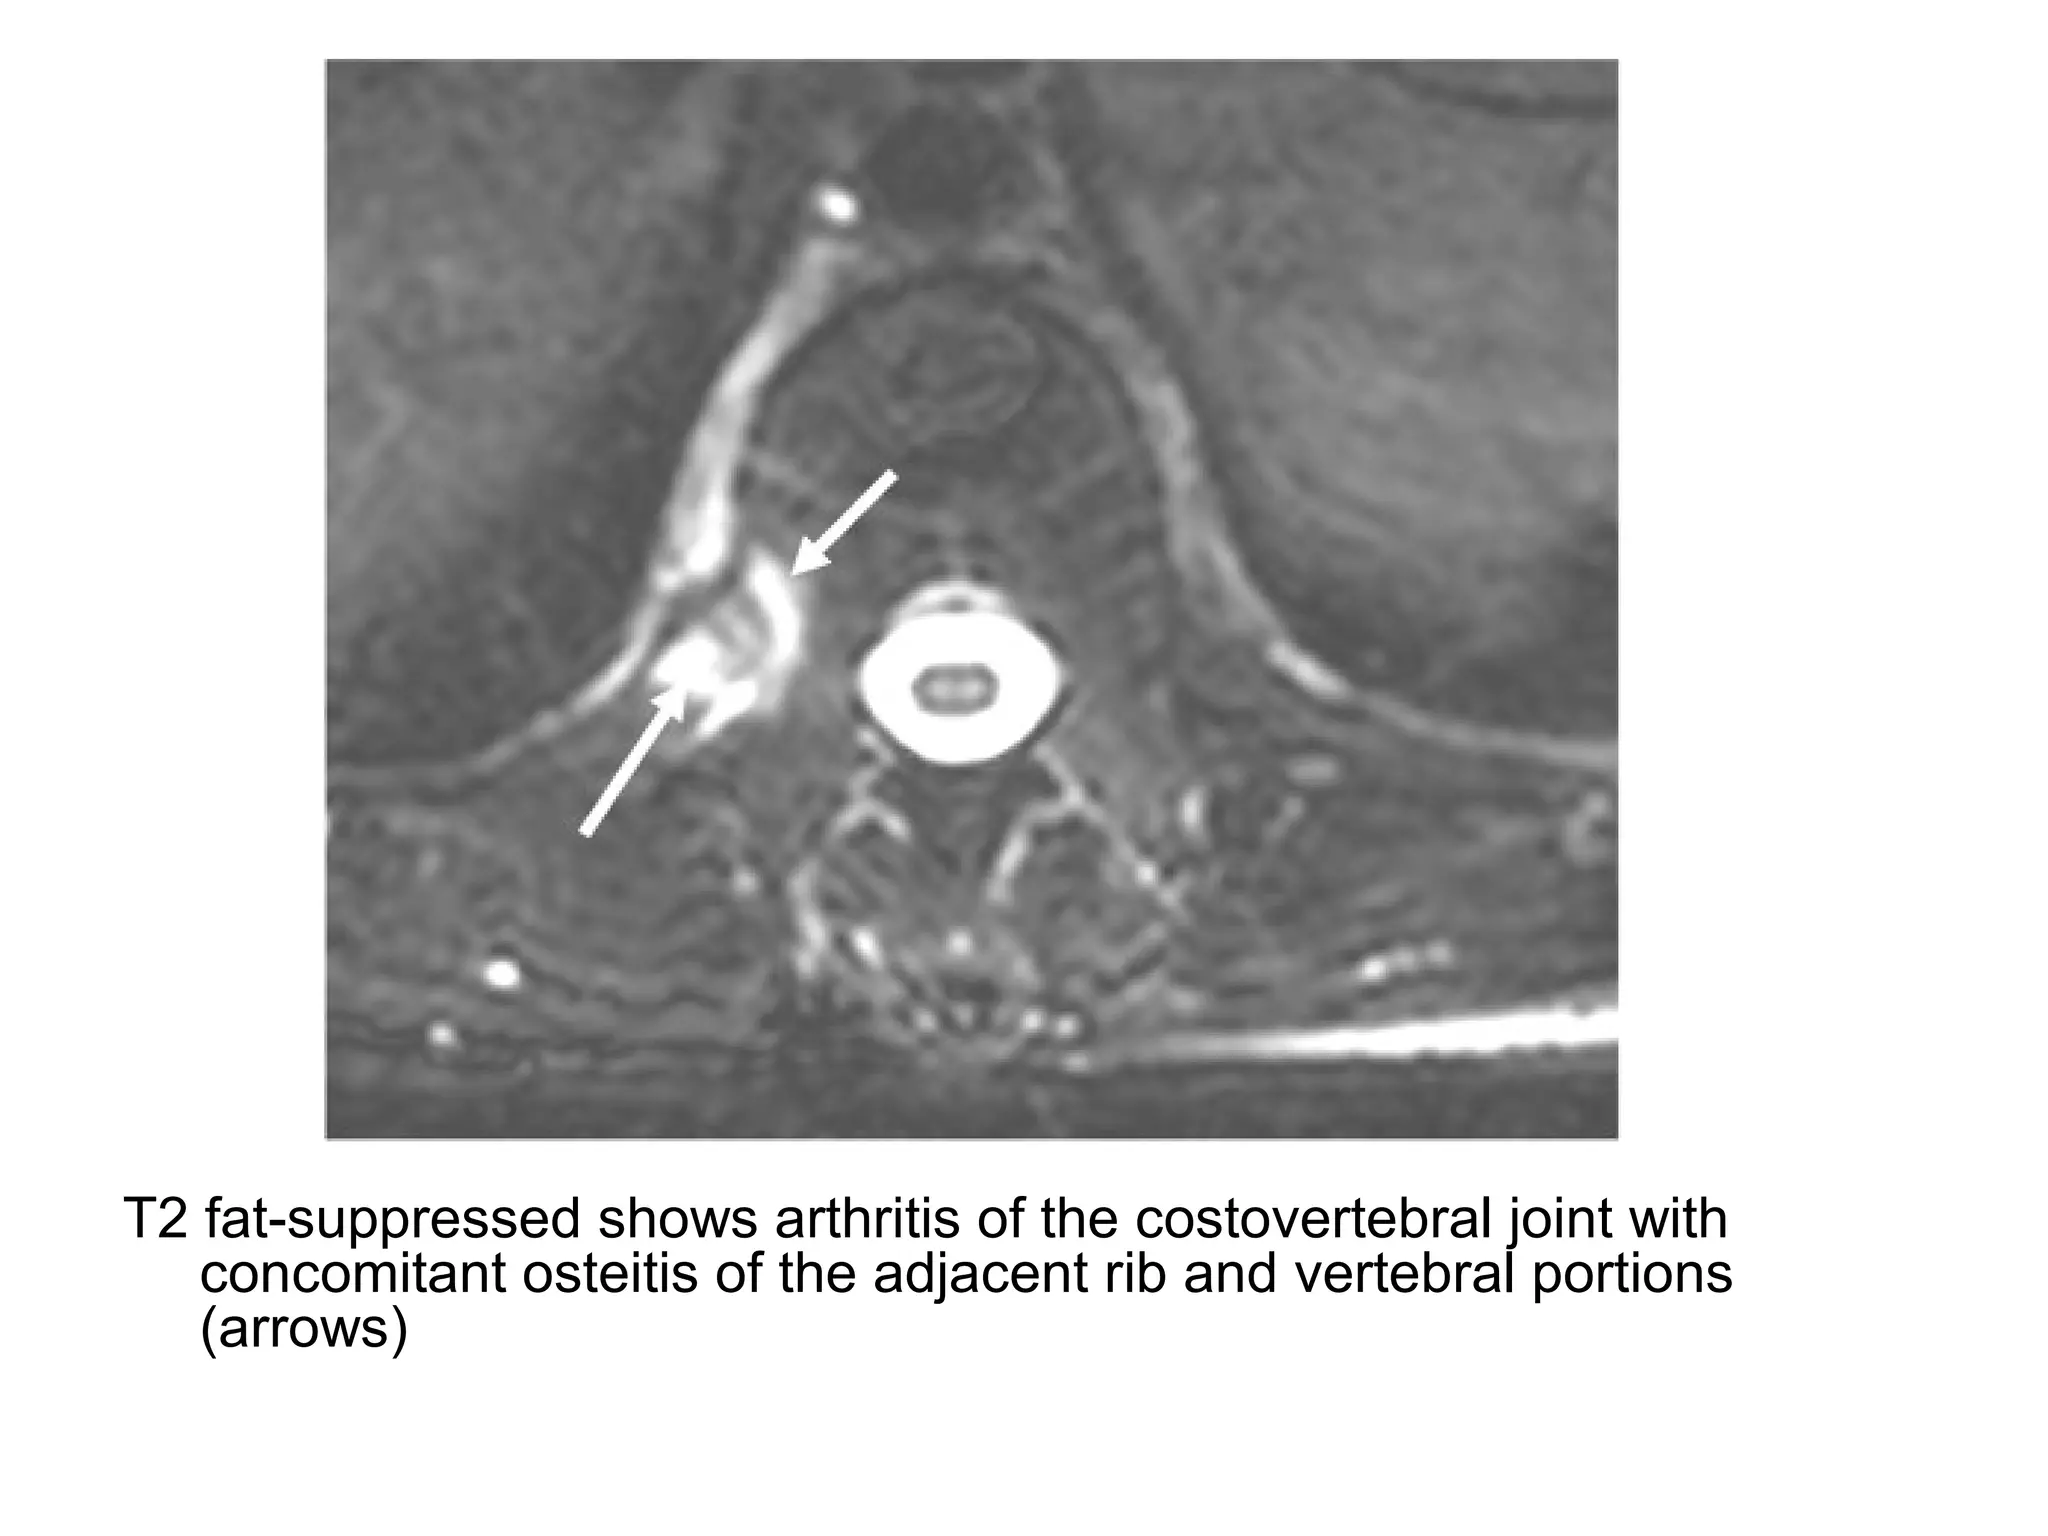

3-Arthritis of the Zygapophyseal Joints :

-May occur with bone marrow edema ,

effusion and erosions and may undergo

ankylosis at the end stage

-The costovertebral and costotransverse

joints may also be involved

T2 fat-suppressed shows arthritis of the costovertebral joint with

concomitant osteitis of the adjacent rib and vertebral portions

(arrows)